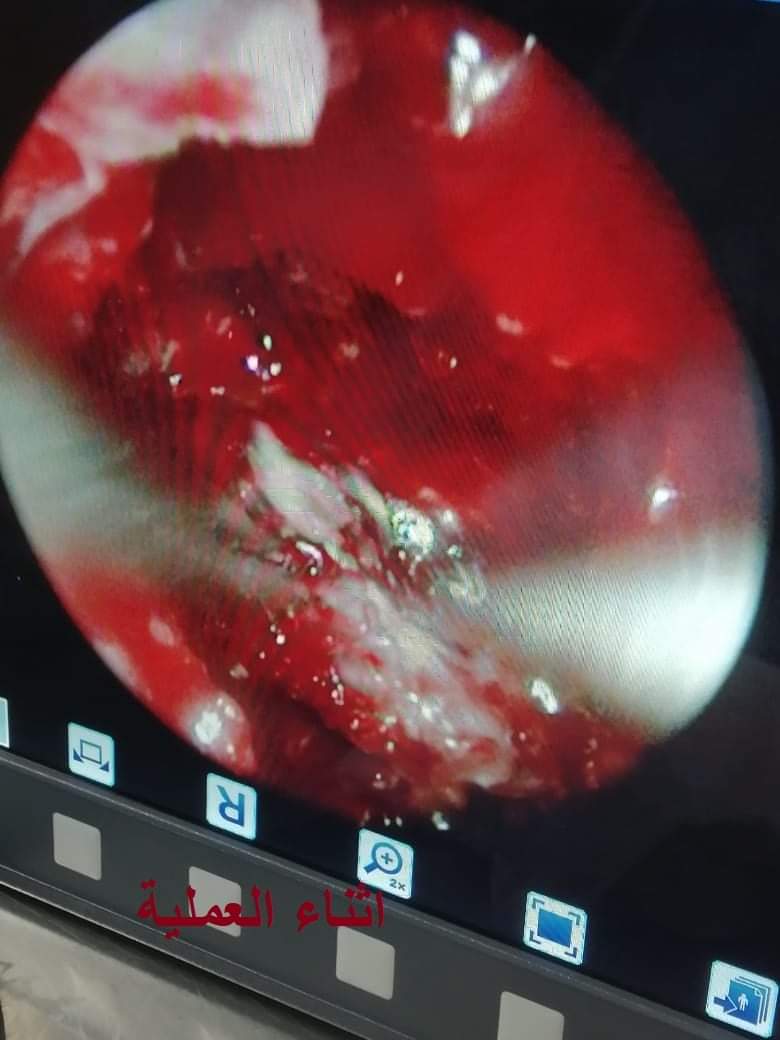

نجح فريق طبي بمستشفيات جامعة بني سويف، في إجراء جراحة نادرة لمريضة تبلغ من العمر 40 عامًا، وكانت تعاني من شلل أعصاب البلع وأعصاب العين وتمت الجراحة عن طريق المنظار الجراحي وتعتبر هذه الحالة من الجراحات النادرة في مصر وتعتبر هذه الحالة هي رقم 4 على مستوى جمهورية مصر العربية، وقد خرجت المريضة بصحة جيدة.

يشار إلى أن هذه خدمة جديدة، تقدمها مستشفيات جامعة بني سويف لمرضى المحافظة.